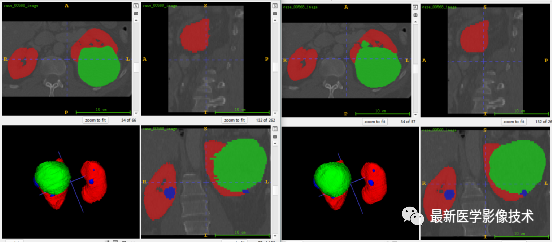

6、测试集分割结果、

左图是金标准结果,右图是预测结果。